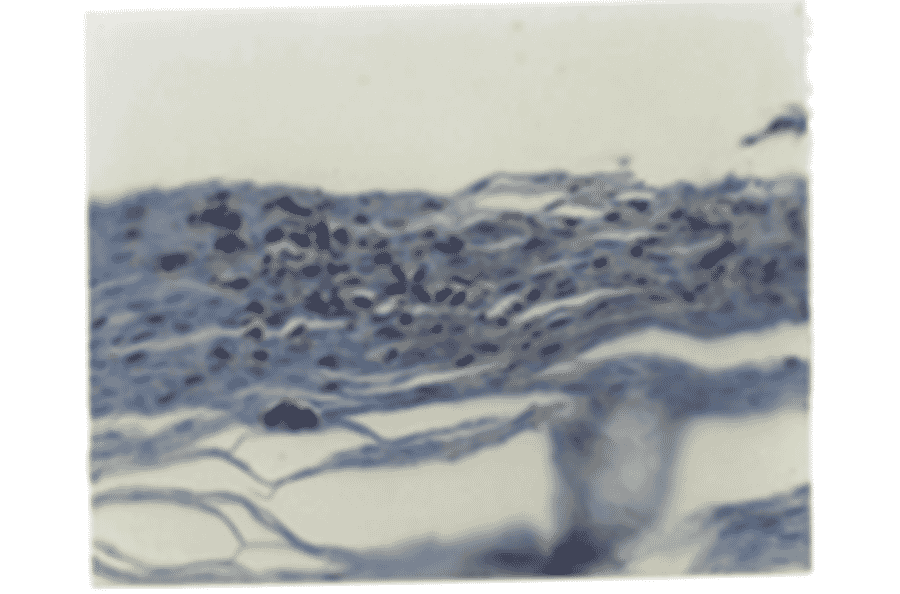

Anti-IL8 Antibody was used to detect IL-8 expression in the stratum corneum of psoriatic skin tissue. IHC result of detection using Anti-IL8 Antibody, biotinylated secondary antibody and avidin-HRP. The specimen was stained with DAB substrate for 5-10 min, and counter-stained with hematoxylin.